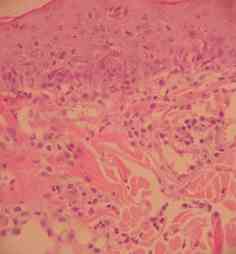

Les biopsies cutanées effectuées à l’aide d’un biopsy-punch au niveau des lésions des babines et de l’ars, (photos 5,6 et 7) montrent une dermatite superficielle périvasculaire hyperplasique avec

• acanthose épidermique diffuse irrégulière (Photo 6)

• infiltration inflammatoire superficielle périvasculaire d’intensité marquée, avec lymphocytes, histiocytes, quelques mastocytes et très nombreux polynucléaires éosinophiles (Photo 7)

cas-de-dermatose-amelioree-par-le-zinc-chez-une-jeune-chienne6Photo 6cas-de-dermatose-amelioree-par-le-zinc-chez-une-jeune-chienne7Photo 7